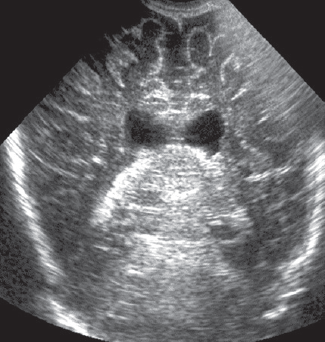

В статье кратко приведены литературные данные и описание клинического динамического наблюдения пациента с тяжелым гипоксическим повреждением головного мозга (от неонатального периода до 4-го месяца жизни) в условиях отделения реанимации и интенсивной терапии новорожденных. Представлены описание клинической картины, особенности пароксизмальных состояний и антиэпилептической терапии, динамика данных нейровизуализации, электроэнцефалографических феноменов, регистрируемых у пациента с церебральной депрессией и структурными церебральными повреждениями. Показана значимость электроэнцефалографического исследования в условиях отделения реанимации как информативного метода оценки церебральной активности у детей раннего возраста с синдромом угнетения центральной нервной системы. Дезорганизация фоновой активности, свидетельствующая о структурных церебральных повреждениях, длительное персистирование медленноволновой активности, выявление эпилептических изменений в виде генерализованных вспышек заостренных волн в диапазоне тета, паттерн альфа-комы, впоследствии сменившийся супрессией фонового паттерна у пациента, являются типичными электрофизиологическими нарушениями, регистрирующимися при тяжелой гипоксической энцефалопатии. В условиях ограничения возможностей визуальной диагностики пациента с нарушением сознания электроэнцефалография остается единственным методом получения информации о функциональном состоянии головного мозга, а данные, полученные при исследовании, — важным прогностическим критерием.